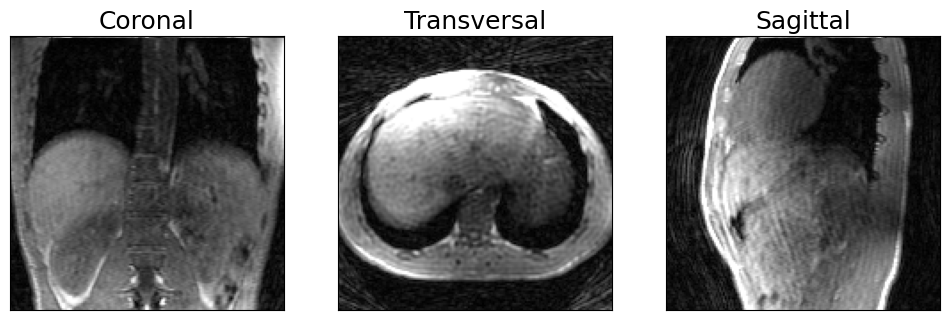

Motion-corrupted image reconstruction

As a first step we will reconstruct the image using all the acquired data which will lead to an image corrupted by respiratory motion.

# Visualize anatomical views of 3D image

show_views(img.rss())